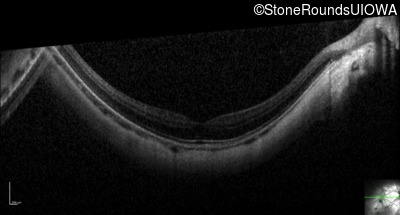

Optical Coherence Tomography - Right - 20/25 -2

Exemplar / OCT Stack

OCT Stack